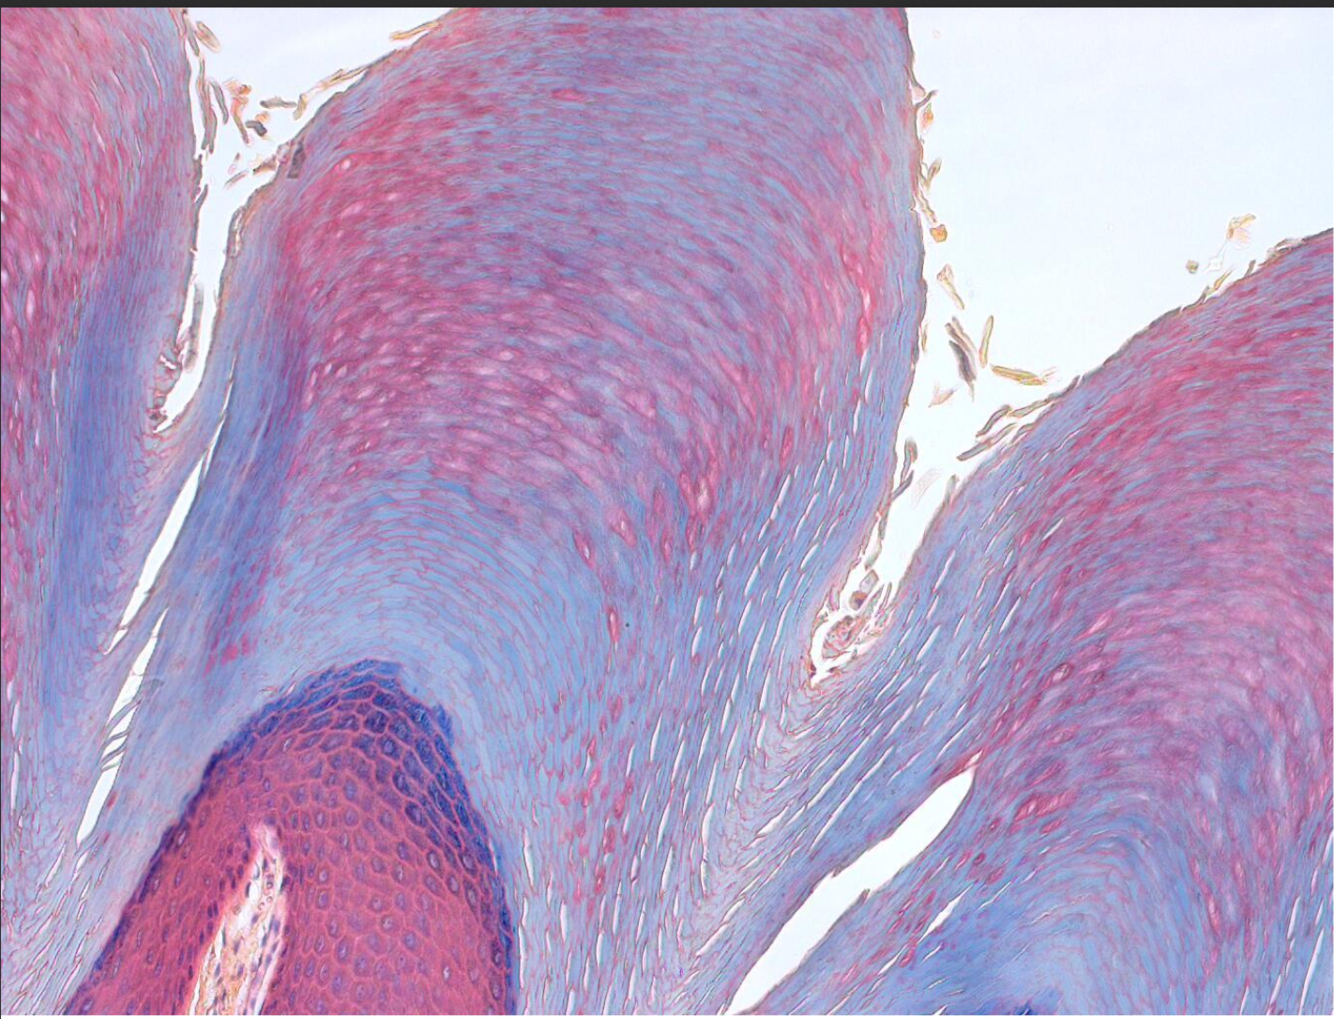

Statified Squamous Keratinized epithelial tissue